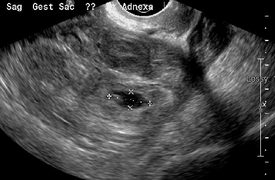

An ultrasound showing a gestational sac with fetal heart in the fallopian tube has a very high specificity of ectopic pregnancy. Transvaginal ultrasonography has a sensitivity of at least 90% for ectopic pregnancy.[1] The diagnostic ultrasonographic finding in ectopic pregnancy is an adnexal mass that moves separately from the ovary. In around 60% of cases, it is an inhomogeneous or a noncystic adnexal mass sometimes known as the "blob sign". It is generally spherical, but a more tubular appearance may be seen in case of hematosalpinx. This sign has been estimated to have a sensitivity of 84% and specificity of 99% in diagnosing ectopic pregnancy.[1] In the study estimating these values, the blob sign had a positive predictive value of 96% and a negative predictive value of 95%.[1] The visualization of an empty extrauterine gestational sac is sometimes known as the "bagel sign", and is present in around 20% of cases.[1] In another 20% of cases, there is visualization of a gestational sac containing a yolk sac and/or an embryo.[1] Ectopic pregnancies where there is visualization of cardiac activity are sometimes termed "viable ectopic".[1]

Ultrasound image showing an ectopic pregnancy where a gestational sac and fetus has been formed.